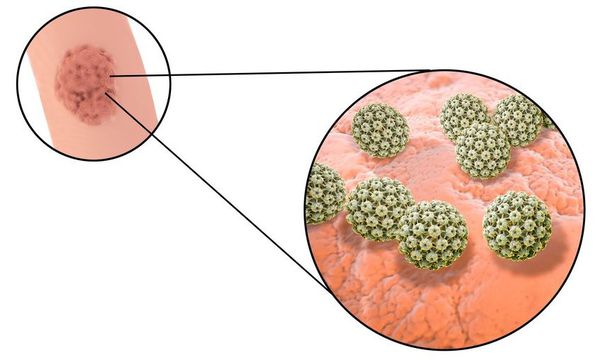

Факторы Риска ВПЧ: Визуальный Обзор и Информация